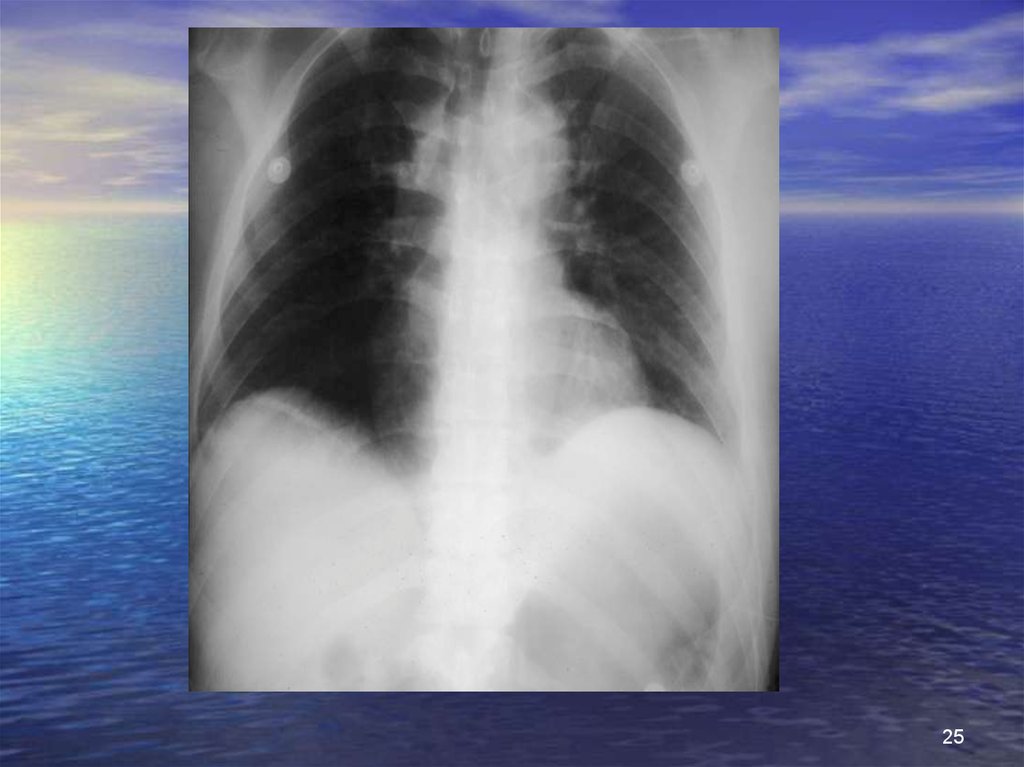

25.

25